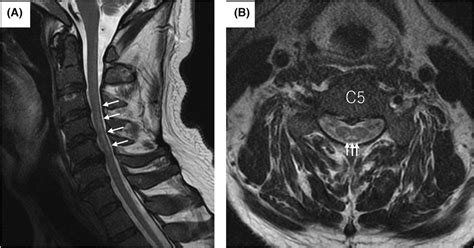

• Magnetic Resonance Imaging (MRI): To visualize the spinal cord and brain for signs of degeneration.

• subacute combined degeneration on mri